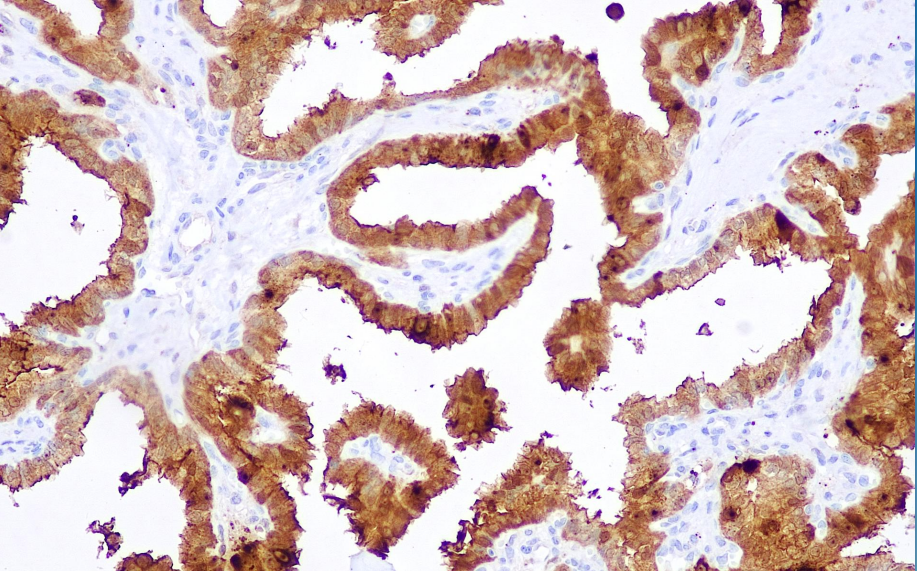

Positive control: papillary thyroid carcinoma

Calectin-3 belongs to the family of beta galactose-binding lectins and is associated with adhesion between similar cells. Also galectin-3 is expressed in mesenchymal large cell lymphoma but not in different types of Hodgkin's disease. Recently, galectin-3 has been used more frequently in combination with CK19 in the diagnosis of papillary thyroid carcinoma.

Galectin-3 antibody reagents can specifically bind to Galectin-3 molecular antigens. Immunohistochemistry kits containing Galectin-3 antibody reagents are suitable for the precise diagnosis of papillary thyroid carcinoma.